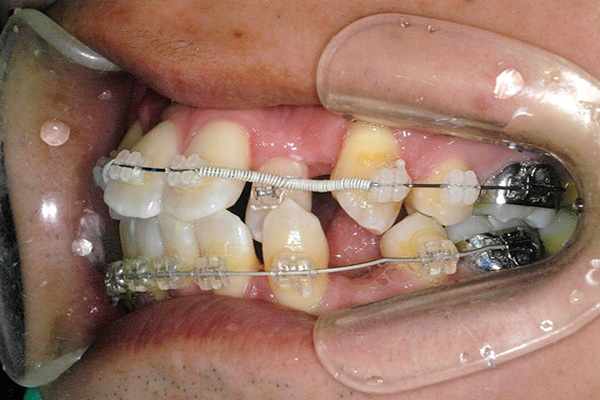

1年5ヶ月後